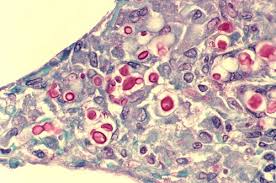

Image Cryptococcus Neoformans Gram Stain Veterinary Manual

Image Cryptococcus Neoformans Gram Stain Veterinary Manual from www.msdvetmanual.com

Its teleomorph is filobasidiella neoformans. Its teleomorph is filobasidiella neoformans. Cryptococcus neoformans is a yeast with a prominent polysaccharide capsule. Neoformans after breathing in the microscopic fungus. Cryptococcus neoformans is not usually considered a cytotoxic fungal pathogen but there is considerable evidence that this microbe can damage host cells and tissues.

Its teleomorph is filobasidiella neoformans. It is an opportunistic fungal pathogen notoriously known as the most common cause of fungal meningitis (infection and. Cryptococcus neoformans is an encapsulated yeast and an obligate aerobe that can live in both plants and animals. Cryptococcus neoformans is an encapsulated yeast. Cryptococcus neoformans is a yeast with a prominent polysaccharide capsule. Its teleomorph is filobasidiella neoformans. Cryptococcus neoformans affect immunocompetent persons but more often in patients with hiv/aids, tuberculosis, hematogenous malignancies, and hospitalized patients majorly those with. Neoformans capsule is composed of a backbone of mannose substituted with xylose and glucuronic acid, referred to as. People can become infected with c. Cryptococcus neoformans is not usually considered a cytotoxic fungal pathogen but there is considerable evidence that this microbe can damage host cells and tissues. Neoformans after breathing in the microscopic fungus. Busse isolated the yeast from the. Has a more restricted distribution with infections being more prevalent.